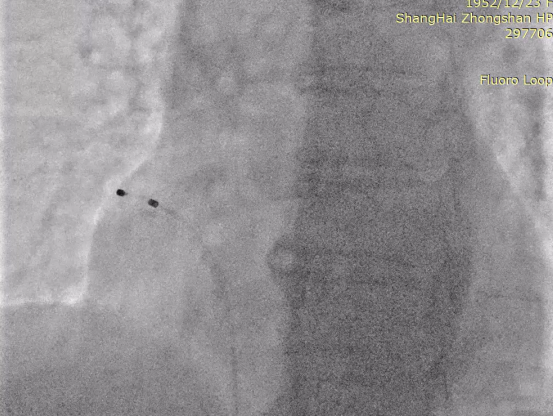

从静脉通路插入临时起搏电极至右心房/右心耳:

RAO

LAO

术中文氏点测试显示患者具有传导阻滞风险(75bpm起搏时出现2:1传导阻滞),与患者及家属充分沟通后,决定升级为Aveir™ DR。